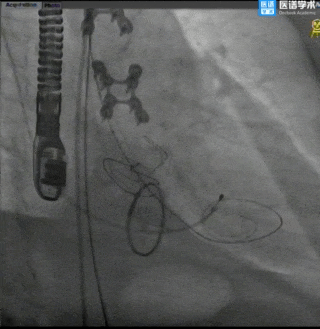

手术过程

主动脉根部造影

球囊预扩

TaurusElite®顺利过弓

TaurusElite®首次释放

TaurusElite®首次回收

TaurusElite®二次释放

TaurusElite®二次回收

TaurusElite®最终释放形态